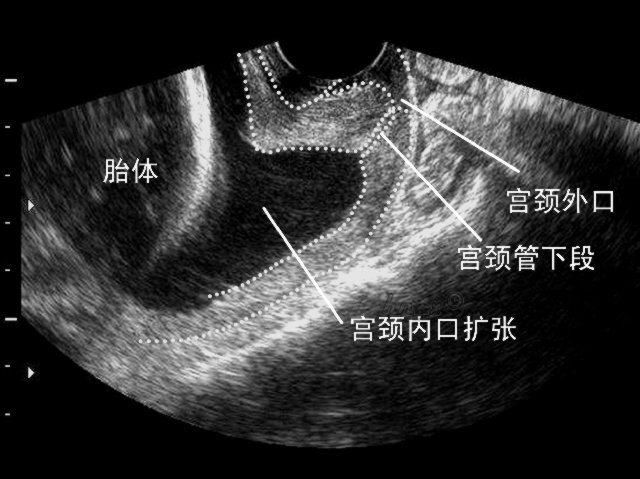

宫颈机能不全

紧急宫颈环扎术 为宝宝拉起人生的第一道保护网_手术_市一医院_患者